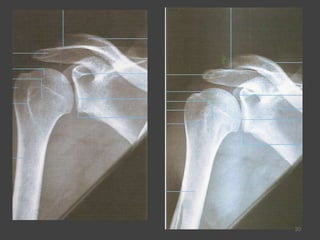

Incidência AP- Ombro Rotação Interna e Externa (RI/RE)21

22

23